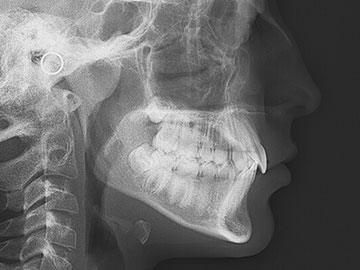

I3.2-Telerradiografias Lateral

La telerradiografía es una radiografía extrabucal, lateral o frontal, que proporciona imágenes muy nítidas de los dientes y huesos de la cara del paciente. En Radiología Dental utilizamos la más vanguardista y revolucionaria tecnología en los sensores digitales de nuestros equipos radiológicos.